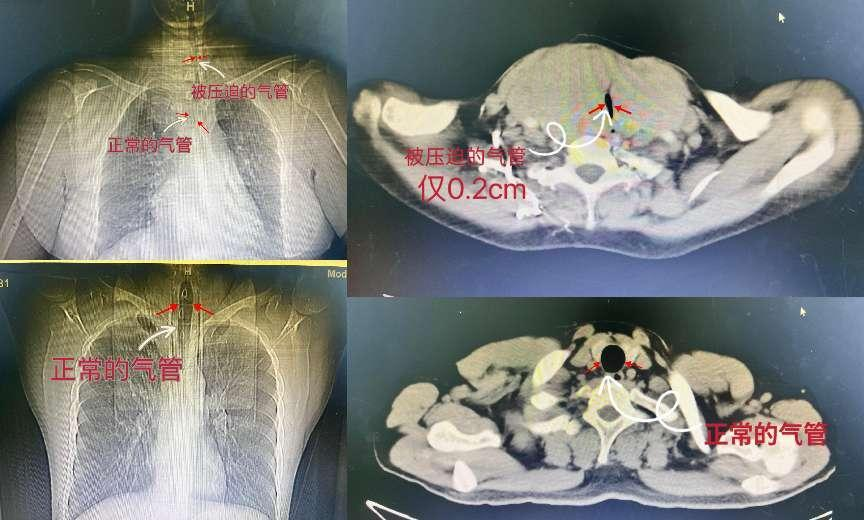

患者唐某某,女,57岁,因“发现颈部肿物20余年”于2024-08-19至芒市人民医院普外科就诊。自诉20年前发现颈部肿物,逐渐增大,已出现吞咽困难及活动后明显的呼吸困难,为缓解症状反复辗转多家医院医治,均未得到有效治疗。在芒市人民医院普外科完善相关术前检查后,初步诊断“巨大结节性甲状腺肿”,CT提示气管被甲状腺肿物压缩严重,最窄部位仅有0.2cm。

为防止患者术中或术后出现气管塌陷等危及生命的并发症,我院进行了多学科讨论会诊,做好了相应的术前准备,于2024年9月1日在麻醉科的支持下全麻行双侧甲状腺切除术,手术顺利,术后病检提示:(左侧、右侧)桥本甲状腺炎;